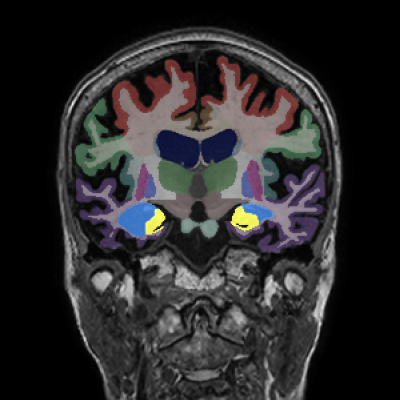

Longitudinal Tracking

Alzheimer's Disease Case Study 2

Retrospective brain volumetric analysis in a female patient diagnosed with Alzheimer’s disease at age 77 showed progressive brain atrophy over a 5-year period. The scans demonstrate temporal cortical atrophy with marked ex-vacuo enlargement of the lateral ventricles.

PATIENT

Female patient diagnosed with Alzheimer's Disease at Age 77

Analysis period

5 years

regions of interest

Temporal cortex

Hippocampus

Inferior lateral ventricles

Age 72

Age 74

Age 77

Lateral ventricle